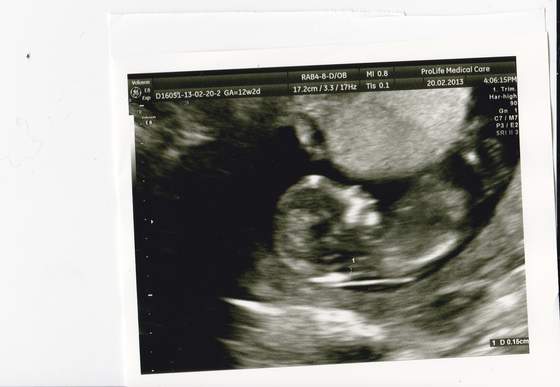

Ja dziś byłam na szybki podgląd mojego paproszka - i seruszko bije, ma 2,1 cm. Co mnie zmartwiło to to, że byłam już na USG dwa razy wcześniej. Wg USG dziecko było najpier jeden a potem dwa "dni starsze niż z OM a dziś dwa dni "młodsze" niż to wynika z OM... Czy to nie jest niepokojące?

Pamiętaj, że wiek z pomiarów zależy tylko i wyłącznie od tego jak gin zaznaczy te plusiki na obrazie płodu/zarodka ;-) Ponadto na wydruku z usg masz obok pomiaru (długość) i wieku ciąży jeszcze takie "widełki"

Zacytuję mój wydruk:

CRL 37,60mm 10w5d 10w1d-11w1d ---> i o to mi chodzi- wielkość dzidzi odpowiada wiekowi ciąży pomiędzy początkiem 11 i 12 tc. A jeszcze kiedyś na monitorze obok wyniku pomiaru widziałam, że się wyświetla +/- 3dni.

Więc spoko, najważniejsze, że serduszko bije